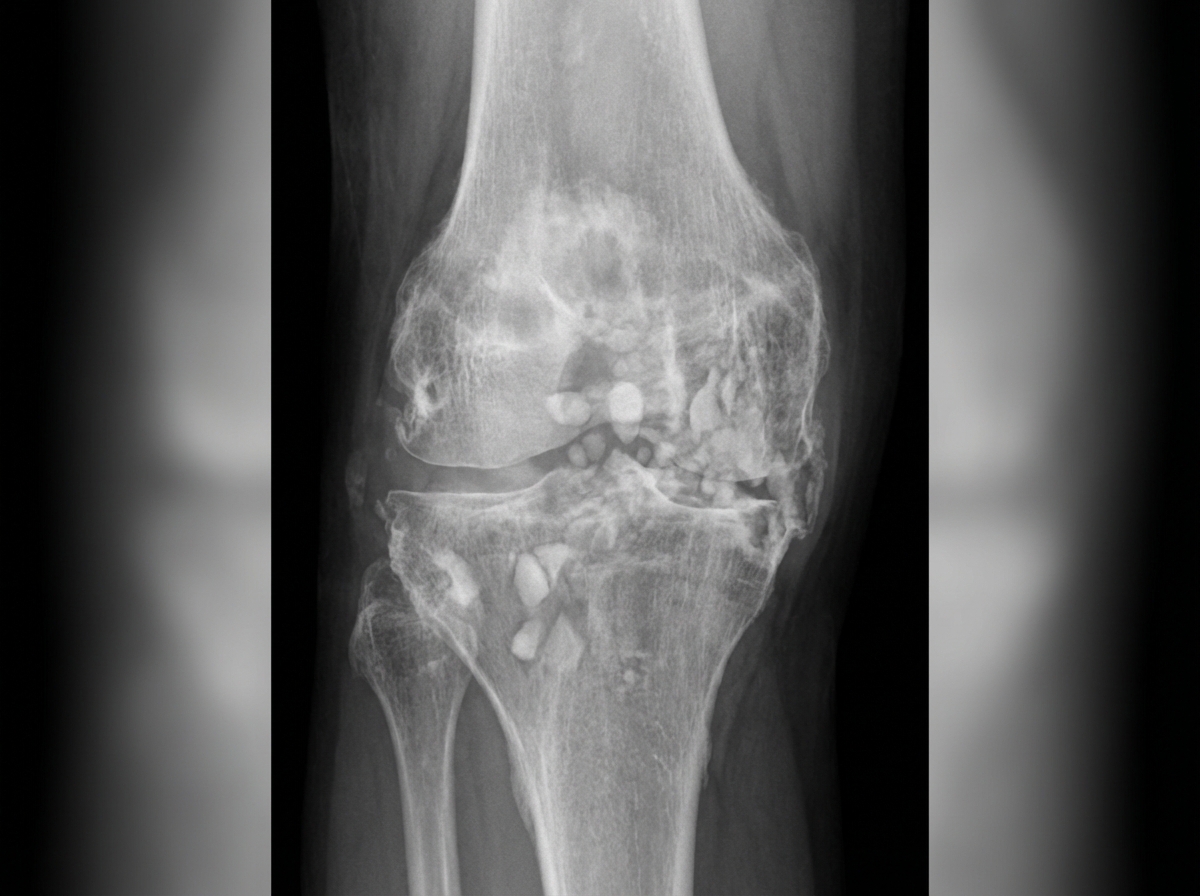

Examine the provided knee X-ray carefully. What is the most likely diagnosis?

Explanation: ***Charcot's disease*** - Shows the classic **5 D's** on X-ray: **Destruction** of joint surfaces, **Disorganization** of normal anatomy, **Density** increase with sclerosis, **Debris** (loose bodies), and **Dislocation** or subluxation - Characterized by **neuropathic arthropathy** with loss of protective sensation leading to progressive joint destruction and **increased bone density** around the affected joint *Tuberculosis (TB)* - X-ray shows **periarticular osteoporosis** and **Phemister triad** (juxta-articular osteoporosis, peripheral erosions, gradual joint space narrowing) - Typically presents with **soft tissue swelling** and **erosive changes** without the sclerosis and debris seen in Charcot's disease *Gout* - X-ray demonstrates **punched-out erosions** with **overhanging edges** and **tophi** calcifications - **Joint space is preserved** in early stages, unlike the destructive changes with increased density seen in neuropathic arthropathy *Rheumatoid arthritis (RA)* - Shows **periarticular osteoporosis**, **joint space narrowing**, and **marginal erosions** without sclerosis - Characterized by **symmetrical involvement** and **absence of increased bone density** or debris formation typical of Charcot's disease